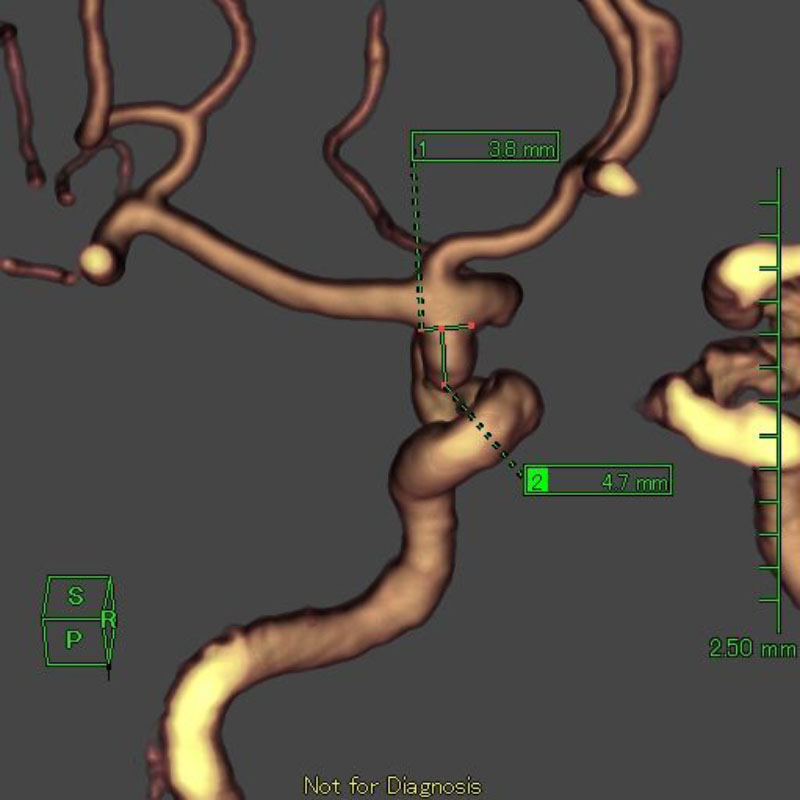

手術後

術後血管撮影